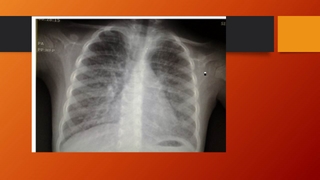

تشخيص :

Pulmonary Alveolar Microlithiasis